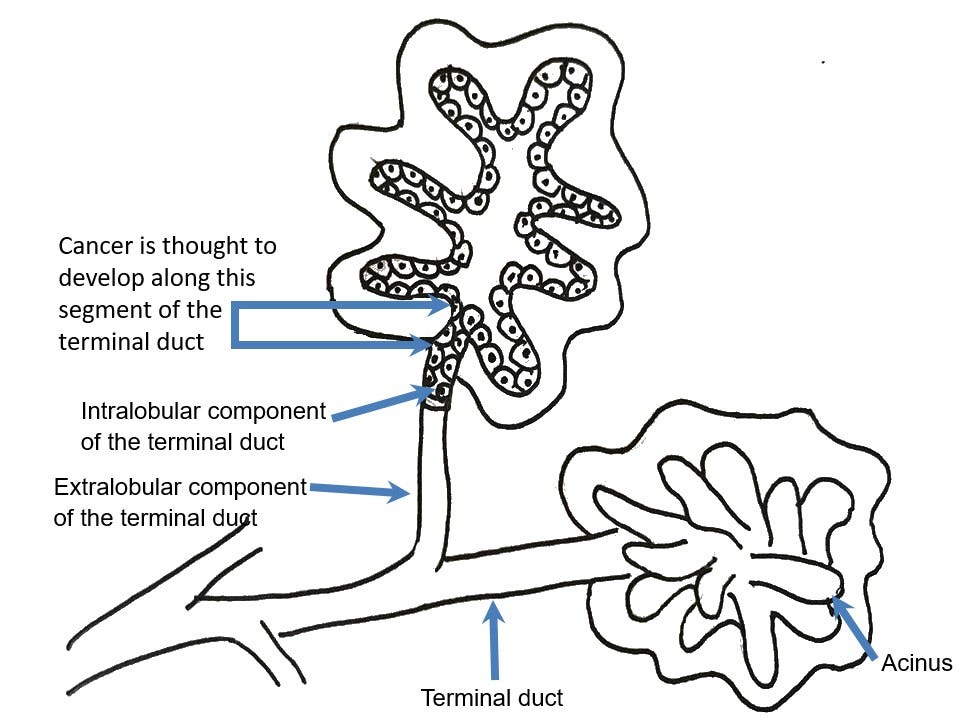

Most cases of breast cancer arise from the progenitor or stem cells of the terminal duct lobular unit, part of the normal anatomy of the female breast:

Common breast cancer types are called ductal or lobular for historical reasons - they no longer accurately reflect our understanding of their origin.